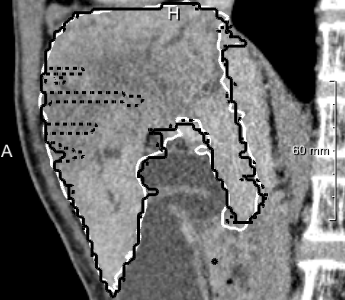

In most cases, the purely slice-wise application of the 2D U-net (dashed contours in 4) does not show any comb artifacts in orthogonal views. However, the ensemble classifier (solid contours) performs significantly better when the appearance is severely abnormal and 3D context is needed. In some cases, it locally performs worse, but has an overall better volumetric overlap (Wilcoxon signed-rank test, ). The ensemble models performed significantly better than the purely 2D transversal model on the same voxel size.

We observed some problems with narrow fissures and gaps (5 left, center), and hypothesized that reducing the resampling target voxel size from 2 mm to 1 mm isotropic could help here. We could not observe qualitative changes, and the volumetric overlap did not change significantly. The MICCAI scores, however, showed significant improvements (Wilcoxon ) due to reduced surface distances, at the expense of higher GPU memory requirements and longer training and classification times.